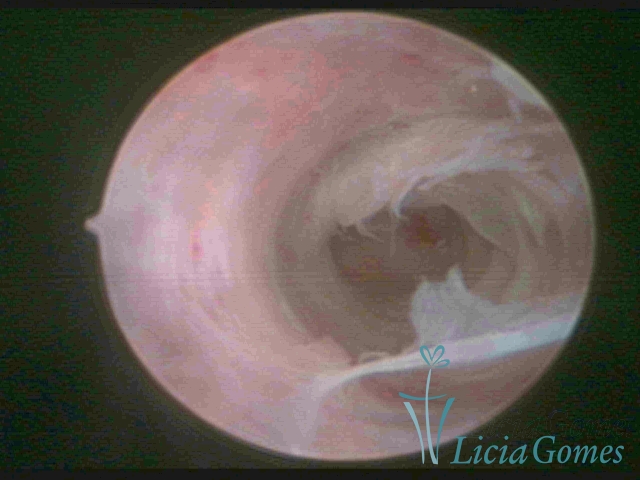

Sinéquia TIPO FIBROSA